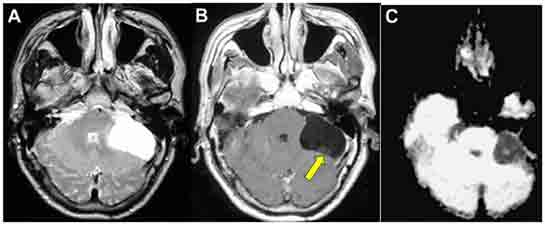

Tanı Yöntemleri Beyinde kist tanısı genellikle görüntüleme yöntemleri kullanılarak konulur. Bu yöntemler arasında en yaygın olanları şunlardır: